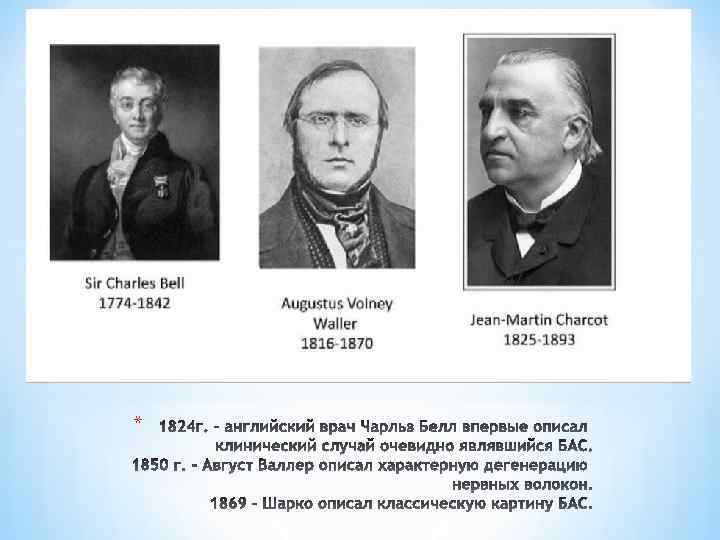

*

*